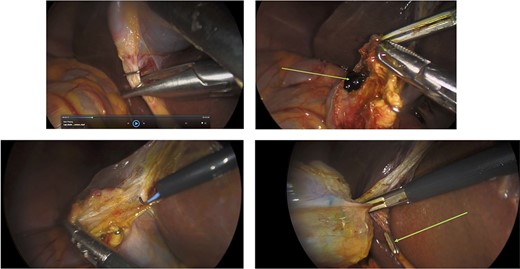

Surgery: gastric wedge resection. (a) laparoscopic entry into the lesser sac through the gastro-colonic ligament (blue arrow). (b) methylene blue markings visible on the serosal layer of the stomach (blue arrows) to delineate the tumour margins. (c) complete mobilization of the gastro-colic and gastro-splenic ligament and visualization of the gastric GIST (green arrow) on the posterior wall of the stomach. (d) macroscopically clear tumour margins post GIST resection. (e) posterior gastric wall sutured closure (yellow arrow).